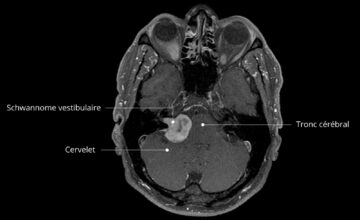

Rééducation vestibulaire : amélioration des résultats symptomatiques et fonctionnels chez les personnes atteintes d’un schwannome vestibulaire : revue systématique

Jayden Yap, BPhty(Hons) , Gretta Palmer, BPhty(Hons) , Kate Graving, BPhty(Hons) , Shona Stone, BPhty(Hons) , Elise M Gane, BPhty(Hons), PhD Abstrait Objectif : Les personnes atteintes d’un schwannome vestibulaire souffrent de vertiges, de troubles de l’équilibre et d’une diminution des fonctions, ce qui entraîne une baisse de leur qualité de vie. D’autres formes d’hypofonctionnement vestibulaire périphérique montrent une amélioration de ces signes […]

Efficacité de la rééducation vestibulaire utilisant un paradigme de rotation unidirectionnelle dans l’asymétrie du réflexe vestibulo-oculaire : revue systématique et méta-analyse

Miriam González-García, Lucía Prieto-Sánchez-de-Puerta, María Alharilla Montilla-Ibáñez, Emilio Domínguez-Durán, Serafín Sánchez-Gómez & Ana Sedeño-Vidal Abstrait Objectif : Une dysfonction vestibulaire unilatérale entraîne une asymétrie significative du réflexe vestibulo-oculaire horizontal (VOR) lors de mouvements rapides de la tête. Ce réflexe peut être amélioré grâce à des exercices de rééducation et à des techniques d’adaptation visuo-vestibulaire. Cette revue systématique vise à évaluer les […]